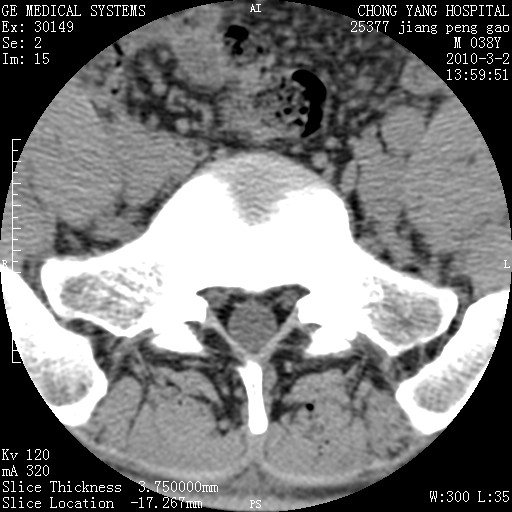

标题: CT24887:M38Y 反复腰痛 无外伤史 未做针灸 竖脊肌为何积气 [打印本页]

标题: CT24887:M38Y 反复腰痛 无外伤史 未做针灸 竖脊肌为何积气

退变,轻度增生/间盘膨出、l5椎后缘软骨结节。

肌间隙积气过多也为退变表现。

椎间盘突出,软组织积气。